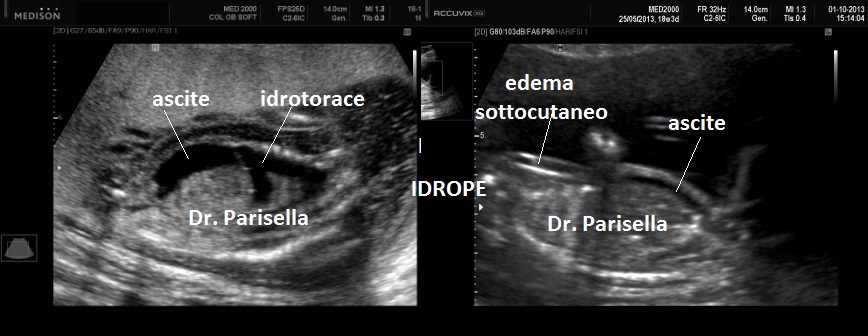

Quella che interessa dal punto di vista della diagnosi ecografica prenatale è l'Osteogenesi Imperfetta tipo II (OMIM 166210) caratterizzata da fragilità ossea con fratture multiple, micromelia severa dovuta alle fratture delle ossa lunghe, ipoplasia toracica severa a volte con fratture costali, ipomineralizzazione diffusa del cranio.  Ecograficamente si manifesta con ossa corte, ricurve e fratturate (le ossa fratturate si presentano angolate); ossa craniche scarsamente ossificate (tanto che la volta cranica può avere una ecogenicità simile a quella della linea mediana) con conseguente migliore evidenza e definizione delle strutture cerebrali e segno caratteristico la deformabilità della teca cranica.;  ipoplasia toracica con fratture costali; IUGR; movimenti fetali scarsi.